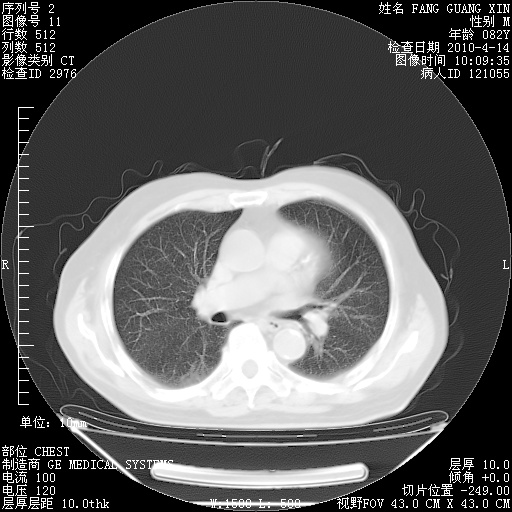

楼主| 发表于 2010-4-28 16:59 | 显示全部楼层

4月28日肺部CT——再次出现类似去年5月9日——透光度降低,(影像科认为)“间质性”改变。

4月28日肺部CT——再次出现类似去年5月9日——透光度降低,“间质性”改变。

1221483 6 .bmp

1221483 7 .bmp

1221483 8 .bmp

1221483 9 .bmp